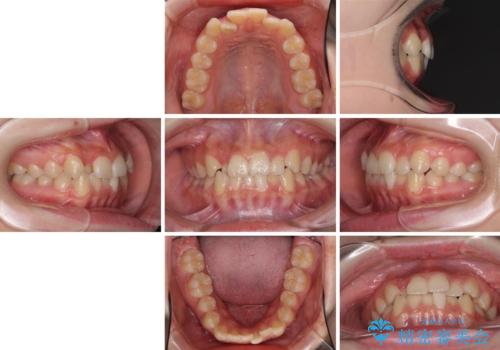

前歯のクロスバイト メタル装置での矯正治療

- 前歯のクロスバイトを気にして来院された患者様です。

前歯の叢生を解消するスペースを獲得するために上顎左右の親知らずを抜歯し、メタルブラケットにて矯正治療を行うこととしました。

当初は1年半程度の治療期間を想定していましたが、上下の正中を合わせていく過程で奥歯の咬みにくさが続いてしまい、2年以上の治療期間を要することとなりました。